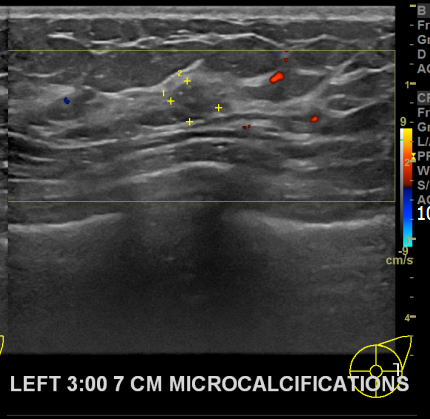

상기환자 유방통증으로 내원하신 40대중반 여성분으로

좌측 조직검사 시행해 상피내암으로 진단되었습니다.